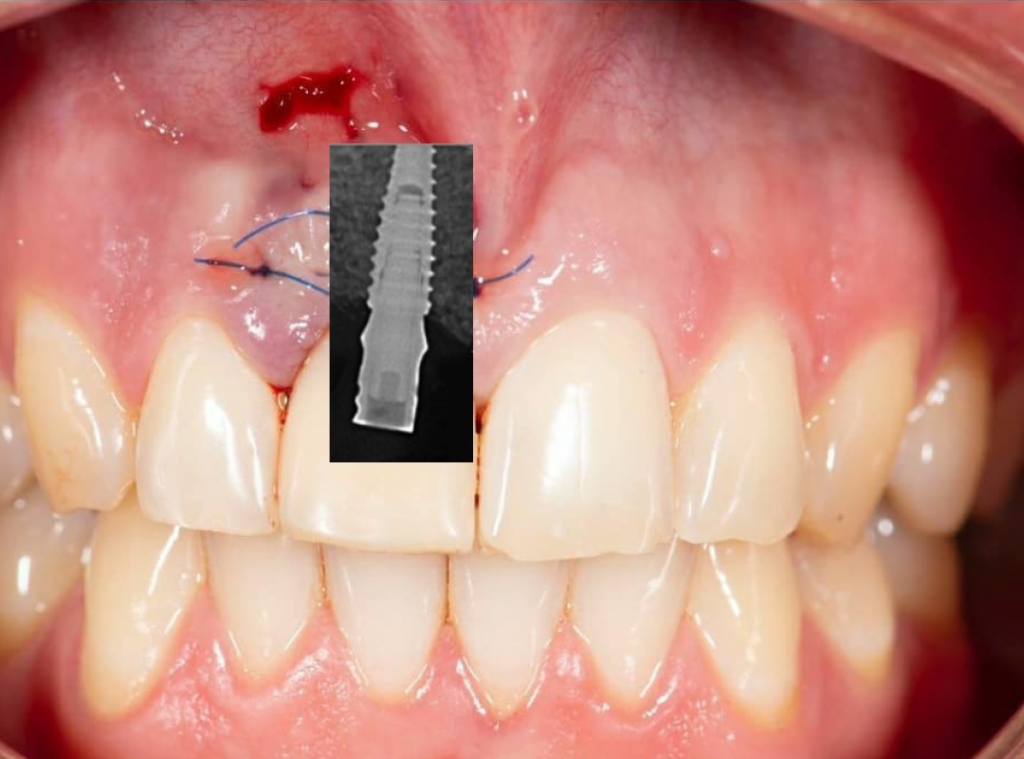

Имплантация AnyRidge во фронтальном отделе.

На КТ была обнаружена трещина корня, не позволяющая вылечить зуб. Было принято решение об удалении зуба с одномоментной имплантацией. Коронковую часть временного зуба восстановили из родного зуба пациента, предварительно отреставрировав его перед установкой.

Срок ношения временной конструкции 4 месяца.